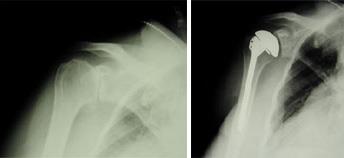

(Left) An x-ray of a healthy shoulder joint. (Right) Osteoarthritis of the shoulder. Note the decreased joint space (arrow).

Total Shoulder Replacement

The typical total shoulder replacement involves replacing the arthritic joint surfaces with a highly polished metal ball attached to a stem, and a plastic socket.

A total shoulder joint replacement.

These components come in various sizes. They may be either cemented or "press fit" into the bone. If the bone is of good quality, your surgeon may choose to use a non-cemented (press-fit) humeral component. If the bone is soft, the humeral component may be implanted with bone cement. In most cases, an all-plastic glenoid (socket) component is implanted with bone cement.

Patients with bone-on-bone osteoarthritis and intact rotator cuff tendons are generally good candidates for conventional total shoulder replacement.

These x-rays were taken before and after total shoulder replacement surgery for osteoarthritis.